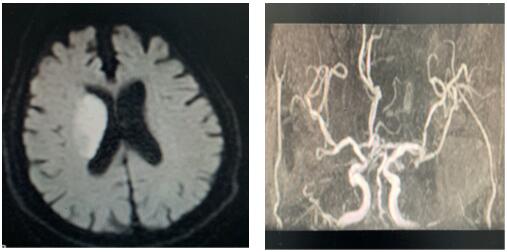

患者治疗前影像图

2020年2月11日,我院卒中中心接到急救电话,一位91岁老人,突发左侧肢体无力,言语不能,卒中急诊李博涛医师迅速判断,考虑急性脑卒中,在NICU王伟伟副主任带领下,确保疫情防范安全,立即开通卒中绿色通道,卒中护理团队井井有条做好溶栓工作,谢小攀医师严密观察患者生命体征,溶栓效果及不良反应,治疗后左侧肢体肌力恢复4级,达到理想效果。为患者在疫情肆虐中紧急发病的慌乱心情中,带来了温暖与希望。